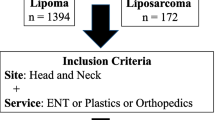

Case identification

We identified cases of lipoblastoma from retrospective review with two sources: (1) the referral case database of the American Institute for Radiologic Pathology (n=49) and (2) a medical record search from a quaternary pediatric medical center, the Children’s Hospital of Philadelphia (n=7), including cases reported between 2011 and 2019. We reviewed all available imaging studies and relevant clinical information and anonymized them in accordance with our institutional review board protocol. The review board approved the study, and the study complied with the Health Insurance Portability and Accountability Act. We also reviewed pathology reports, including testing for PLAG1 mutations when it was performed. Inclusion criteria consisted of histopathological confirmation of lipoblastoma or lipoblastomatosis, availability of cross-sectional imaging consisting of CT or MRI prior to resection, and documentation of clinical presentation. Cases were excluded if pathology was discordant or inconclusive for lipoblastoma, if CT or MRI was not performed prior to resection, or if insufficient diagnostic images were available for review. Imaging protocols were heterogeneous because of the referral nature of the included database. At least T1-weighted non-fat-suppressed and either T2-weighted or short tau inversion recovery (STIR) acquisitions were required for MRI inclusion in this study.

Complex fat-containing lesions in young children should not be confused for malignant entities such as well-differentiated or myxoid liposarcoma, which are exceedingly rare in young children, especially infants [17]. Other nonmalignant entities to be considered include hibernoma and spindle cell lipoma, although both occur in older adults with more restricted anatomical distributions than lipoblastoma [3, 17]. As a general rule, the primary diagnostic consideration of fat-containing soft-tissue masses in children should be lipoblastoma.